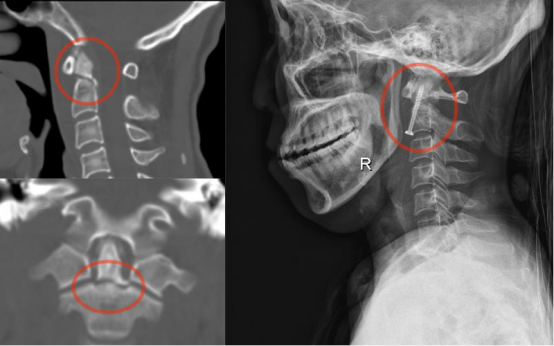

如齿状突骨折、寰枢椎骨折(脱位)、寰枕畸形等,上颈椎失稳可引起严重的脊髓功能障碍。上颈椎前路或后路手术骨折复位固定,重建脊柱稳定性,解除脊髓压迫。

注:手术前CT示齿状突骨折,手术予微创前路中空加压螺钉内固定,术后照片显示骨折复位满意。

注:手术前CT示寰枢椎脱位,椎管狭窄,手术予后路寰枢椎螺钉内固定,术后照片显示骨折复位满意。